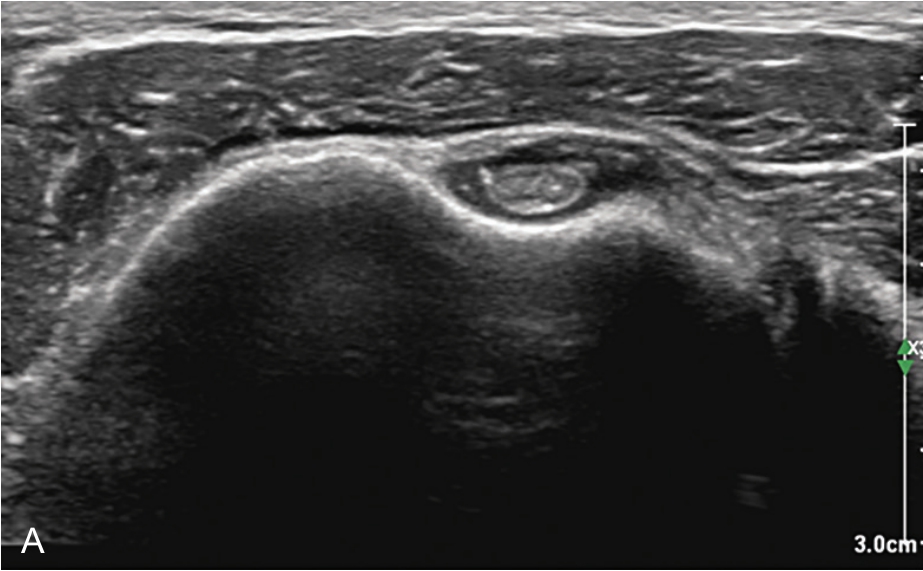

▲ 图2-3-1 超声引导下肱二头肌长头腱鞘介入治疗操作图(一)

探头横切,显示肱二头肌长头腱短轴,穿刺针由外向内平面内进针

▲ 图2-3-4 超声引导下肱二头肌长头腱鞘介入治疗超声图(一)

A.二维超声:肱二头肌腱鞘内少量积液及滑膜增生;B.超声多普勒:肱二头肌腱鞘内及周围血流较丰富;C.平面内进针法,针尖进入肱二头肌长头腱鞘内;D注射治疗后腱鞘液体增多